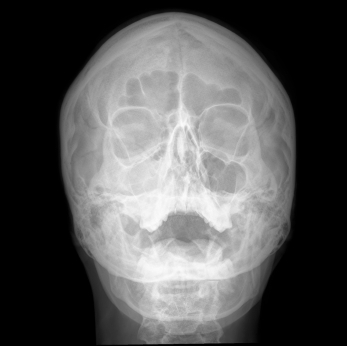

Гайморит это воспаление или инфекция придаточных пазух носа. Пазухи полости лицевой части черепа, и выстланы слизистой оболочкой. Гайморит это воспаление или инфекция этих пазух. Она развивается чаще всего в гайморовых пазух (под глазами) и решетчатой пазухи. В более серьезных инфекций инфекция может повлечь за собой кости (остеомиелита). Редко инфекция может распространиться на головной мозг и быть опасными для жизни.

ДИАГНОСТИКА

Изучение истории болезни и медицинский осмотр не проводятся. Порой КТ или МРТ будет сделано.